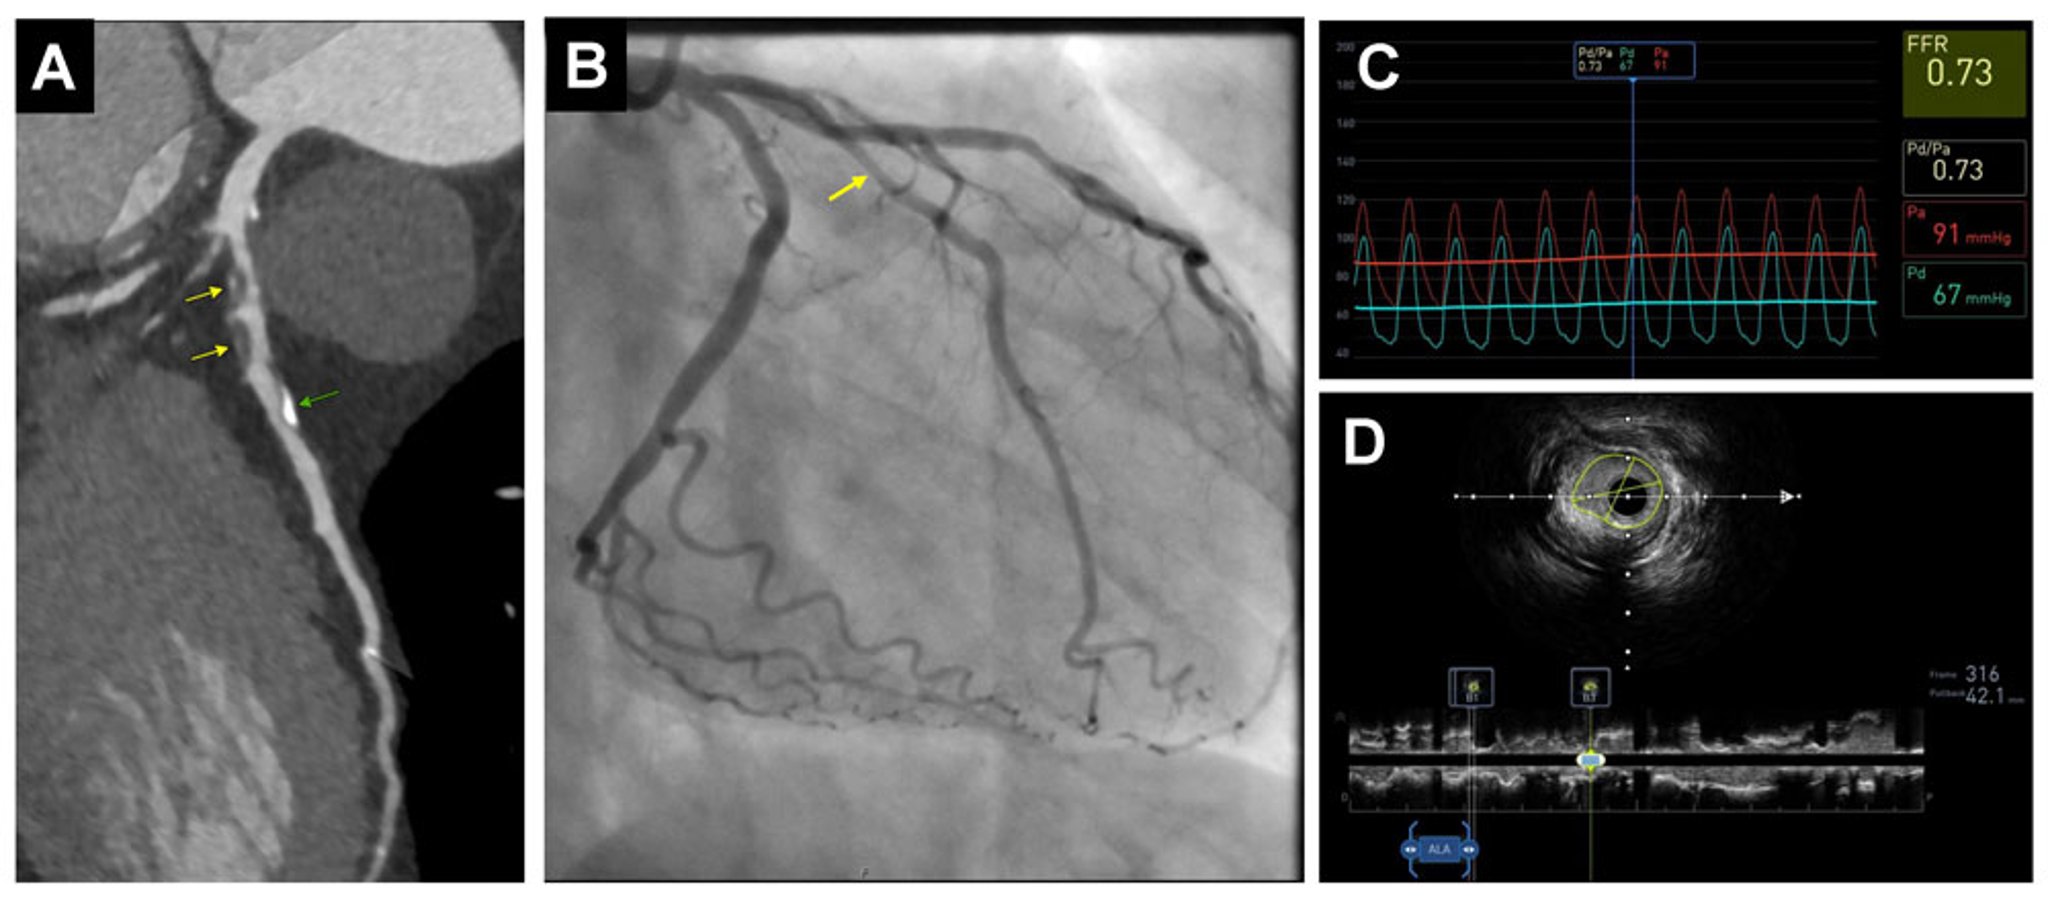

• CT angiography (CTA): CTA uses iodinated contrast-enhanced CT to evaluate atherosclerotic plaque morphology and detect stenosis severity with high spatial resolution. This technique involves ionizing radiation and can be applied to any vascular bed, making it ideal for small, mobile vascular beds like the coronary arteries.

• CT fractional flow reserve (FFR): This technique combines CTA with computational fluid dynamics to assess the physiologic significance of coronary artery stenoses by estimating the pressure drop across a coronary lesion.

• Invasive angiography: A catheter is inserted at the origin of the artery being investigated and iodinated contrast is injected. This technique allows the severity of stenosis to be estimated. In addition, therapeutic interventions, including thrombectomy and angioplasty, can be conducted.

• Intravascular ultrasound (IVUS): An intravascular ultrasound transducer is used to assess the composition and extent of atherosclerotic plaques and to guide intravascular procedures.

• Fractional flow reserve (FFR): A pressure wire is used to evaluate the hemodynamic significance of a stenosis. FFR is based on the ratio of pressure distal and proximal to a stenosis in the presence of maximal blood flow (hyperemia, typically induced by adenosine). In coronary arteries, an FFR ≤ 0.80 indicates a hemodynamically significant stenosis.